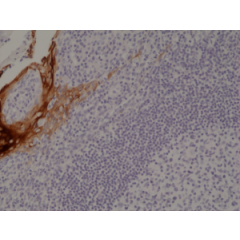

anti-Cytokeratin-7 (human), Rabbit Monoclonal (RM284)

anti-Cytokeratin-7 (human), Rabbit Monoclonal (RM284)

REV-31-1167-00 REV-31-1167-00-R100 100 µl CHF 468.00